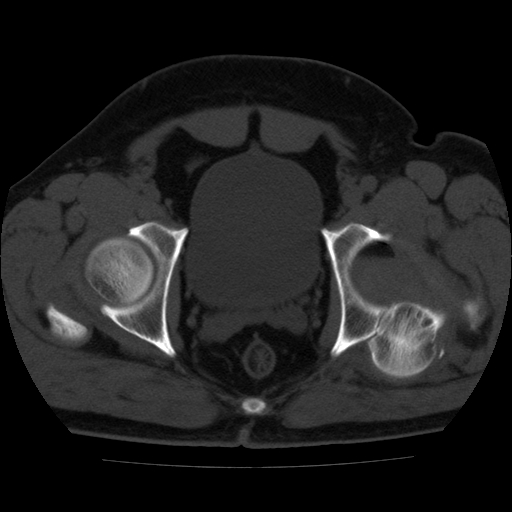

标题: CT21643:男,42岁,车祸伤后左髋关节疼痛剧烈1小时。 [打印本页]

男,42岁,车祸伤后左髋关节疼痛剧烈1小时。

左髋关节脱位并髋臼骨折,左髋关节积血。

左髋关节后脱位并髋臼骨折,左髋关节积血

左髋关节后脱位,大小转子皮质撕脱骨折,关节腔“脂血症”,左侧盆底少量积血,左侧髋臼邻关节囊肿。

左髋关节后脱位并髋臼骨折、股骨头前方骨折,左髋关节积血 。

左髋关节(股骨头)后脱位,并髋臼及股骨头骨折,左髋关节积血。

左髋关节后脱位并髋臼后缘骨折、股骨头前方骨折,左髋关节积血 。我遇到过一例。